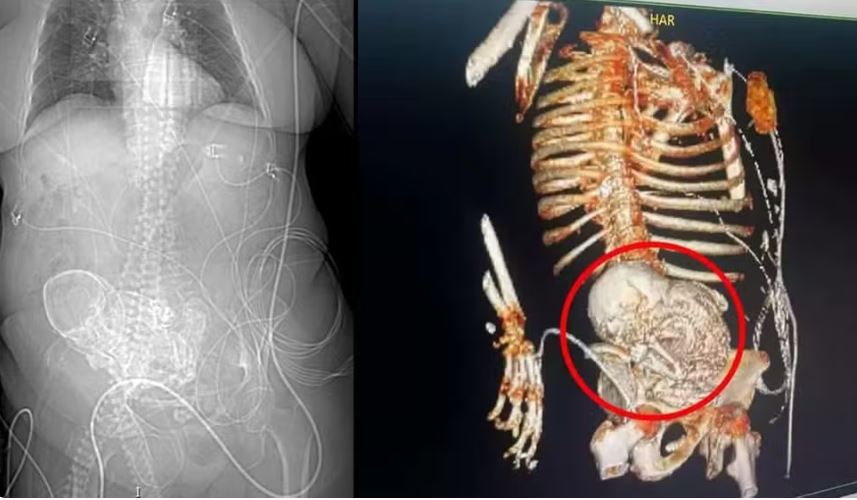

A princípio, os médicos suspeitaram de câncer, mas ao realizar uma tomografia 3D, a equipe identificou o feto no abdômen, em estado de calcificação. O obstetra realizou uma cirurgia de emergência para remover o feto e a idosa foi encaminhada à UTI logo depois.

Porém, ela não resistiu e morreu no dia seguinte. Segundo o médico e secretário de Saúde de Ponta Porã, Patrick Derzi, a condição da mulher, conhecida como litopedia, é raríssima e ocorre quando a gravidez se desenvolve no abdômen ao invés do útero.